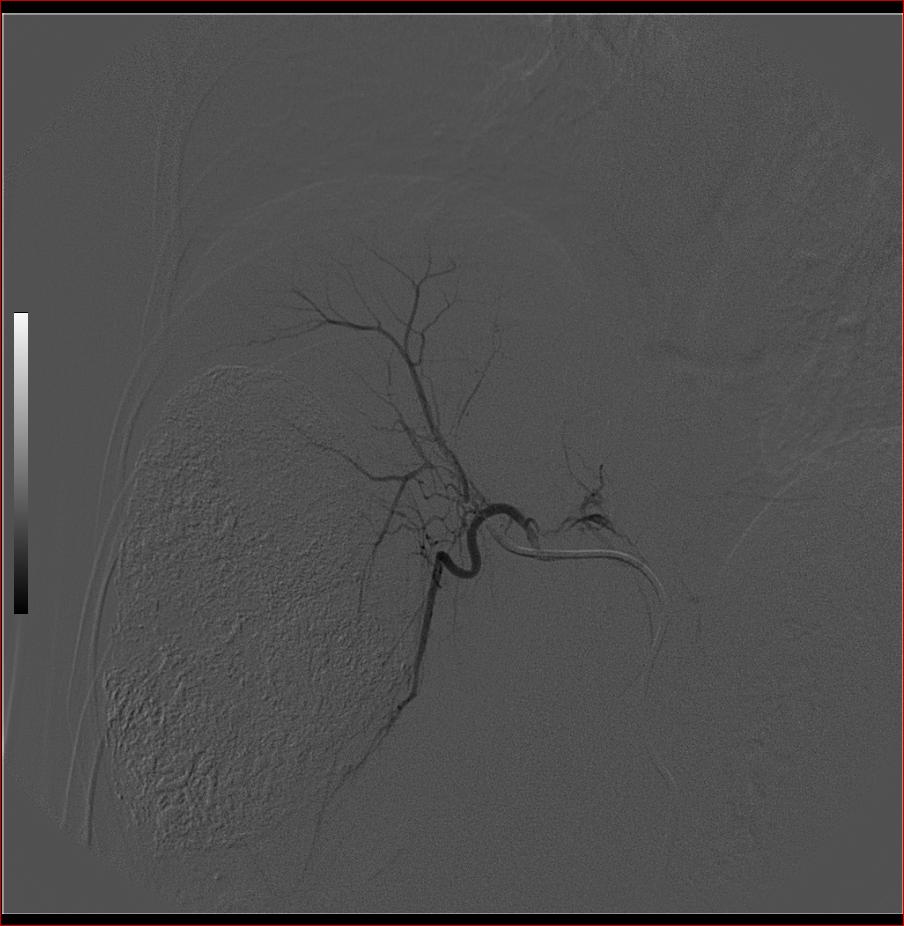

标题: DSA0138:F38Y,肝脏病变

第一次:

好牛的,右肝动脉发自肠系膜上动脉,不用微导管分次进行末梢栓塞,肿瘤染色完整。再次学习了。